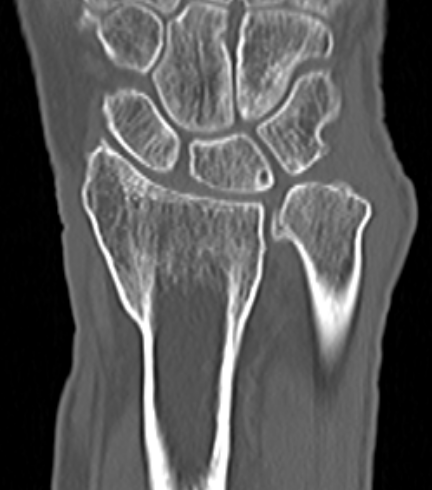

CT